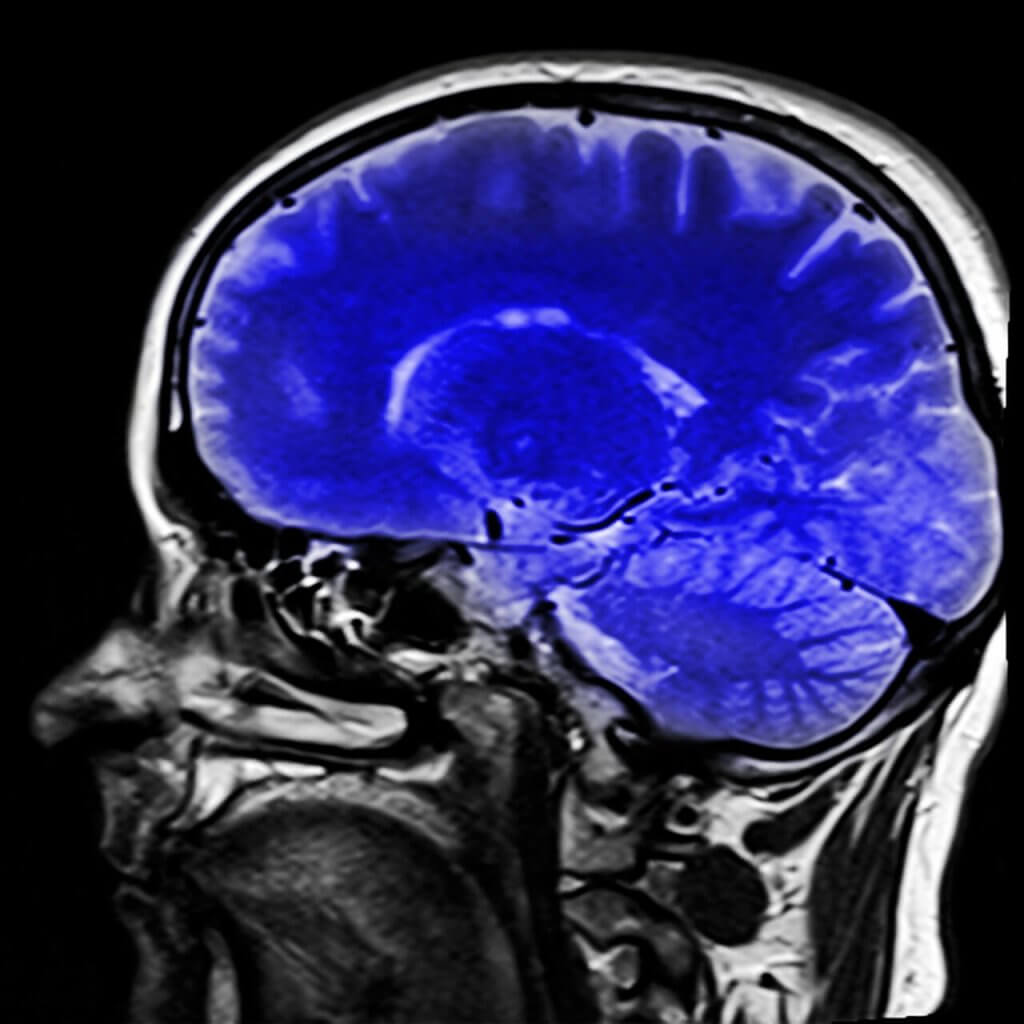

On olemassa neurologisia testejä, jotka auttavat lääkäreitä tekemään diagnoosin tästä oireyhtymästä. Magneettikuvaus voi osoittaa millainen halvaus tapahtui ja tämä auttaa heitä määrittämään mikä oireyhtymä on kyseessä.